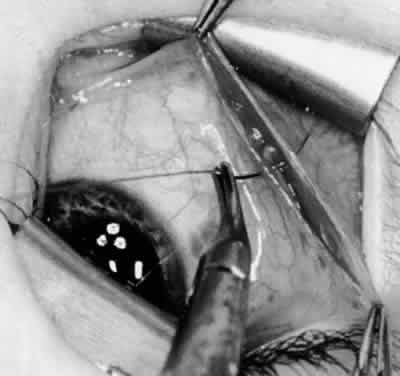

Fig. 3. The eye is retracted superonasally with the 4-0 silk traction suture. The suture is attached to the drapes with a hemostat. A Stevens hook is placed along the inferior border of the lateral rectus muscle and drawn temporally. A von Graefe hook is placed within the incision and drawn inferotemporally to expose the inferior oblique muscle.

Fig. 4. A stiff iris repositor can be placed against the sclera to depress the sclera and enhance the view of the inferior oblique muscle. The inferior temporal vortex vein adjacent to the Stevens hook is retracting tissue along the inferior border of the lateral rectus muscle. The second Stevens hook is pointing to the inferior oblique muscle.